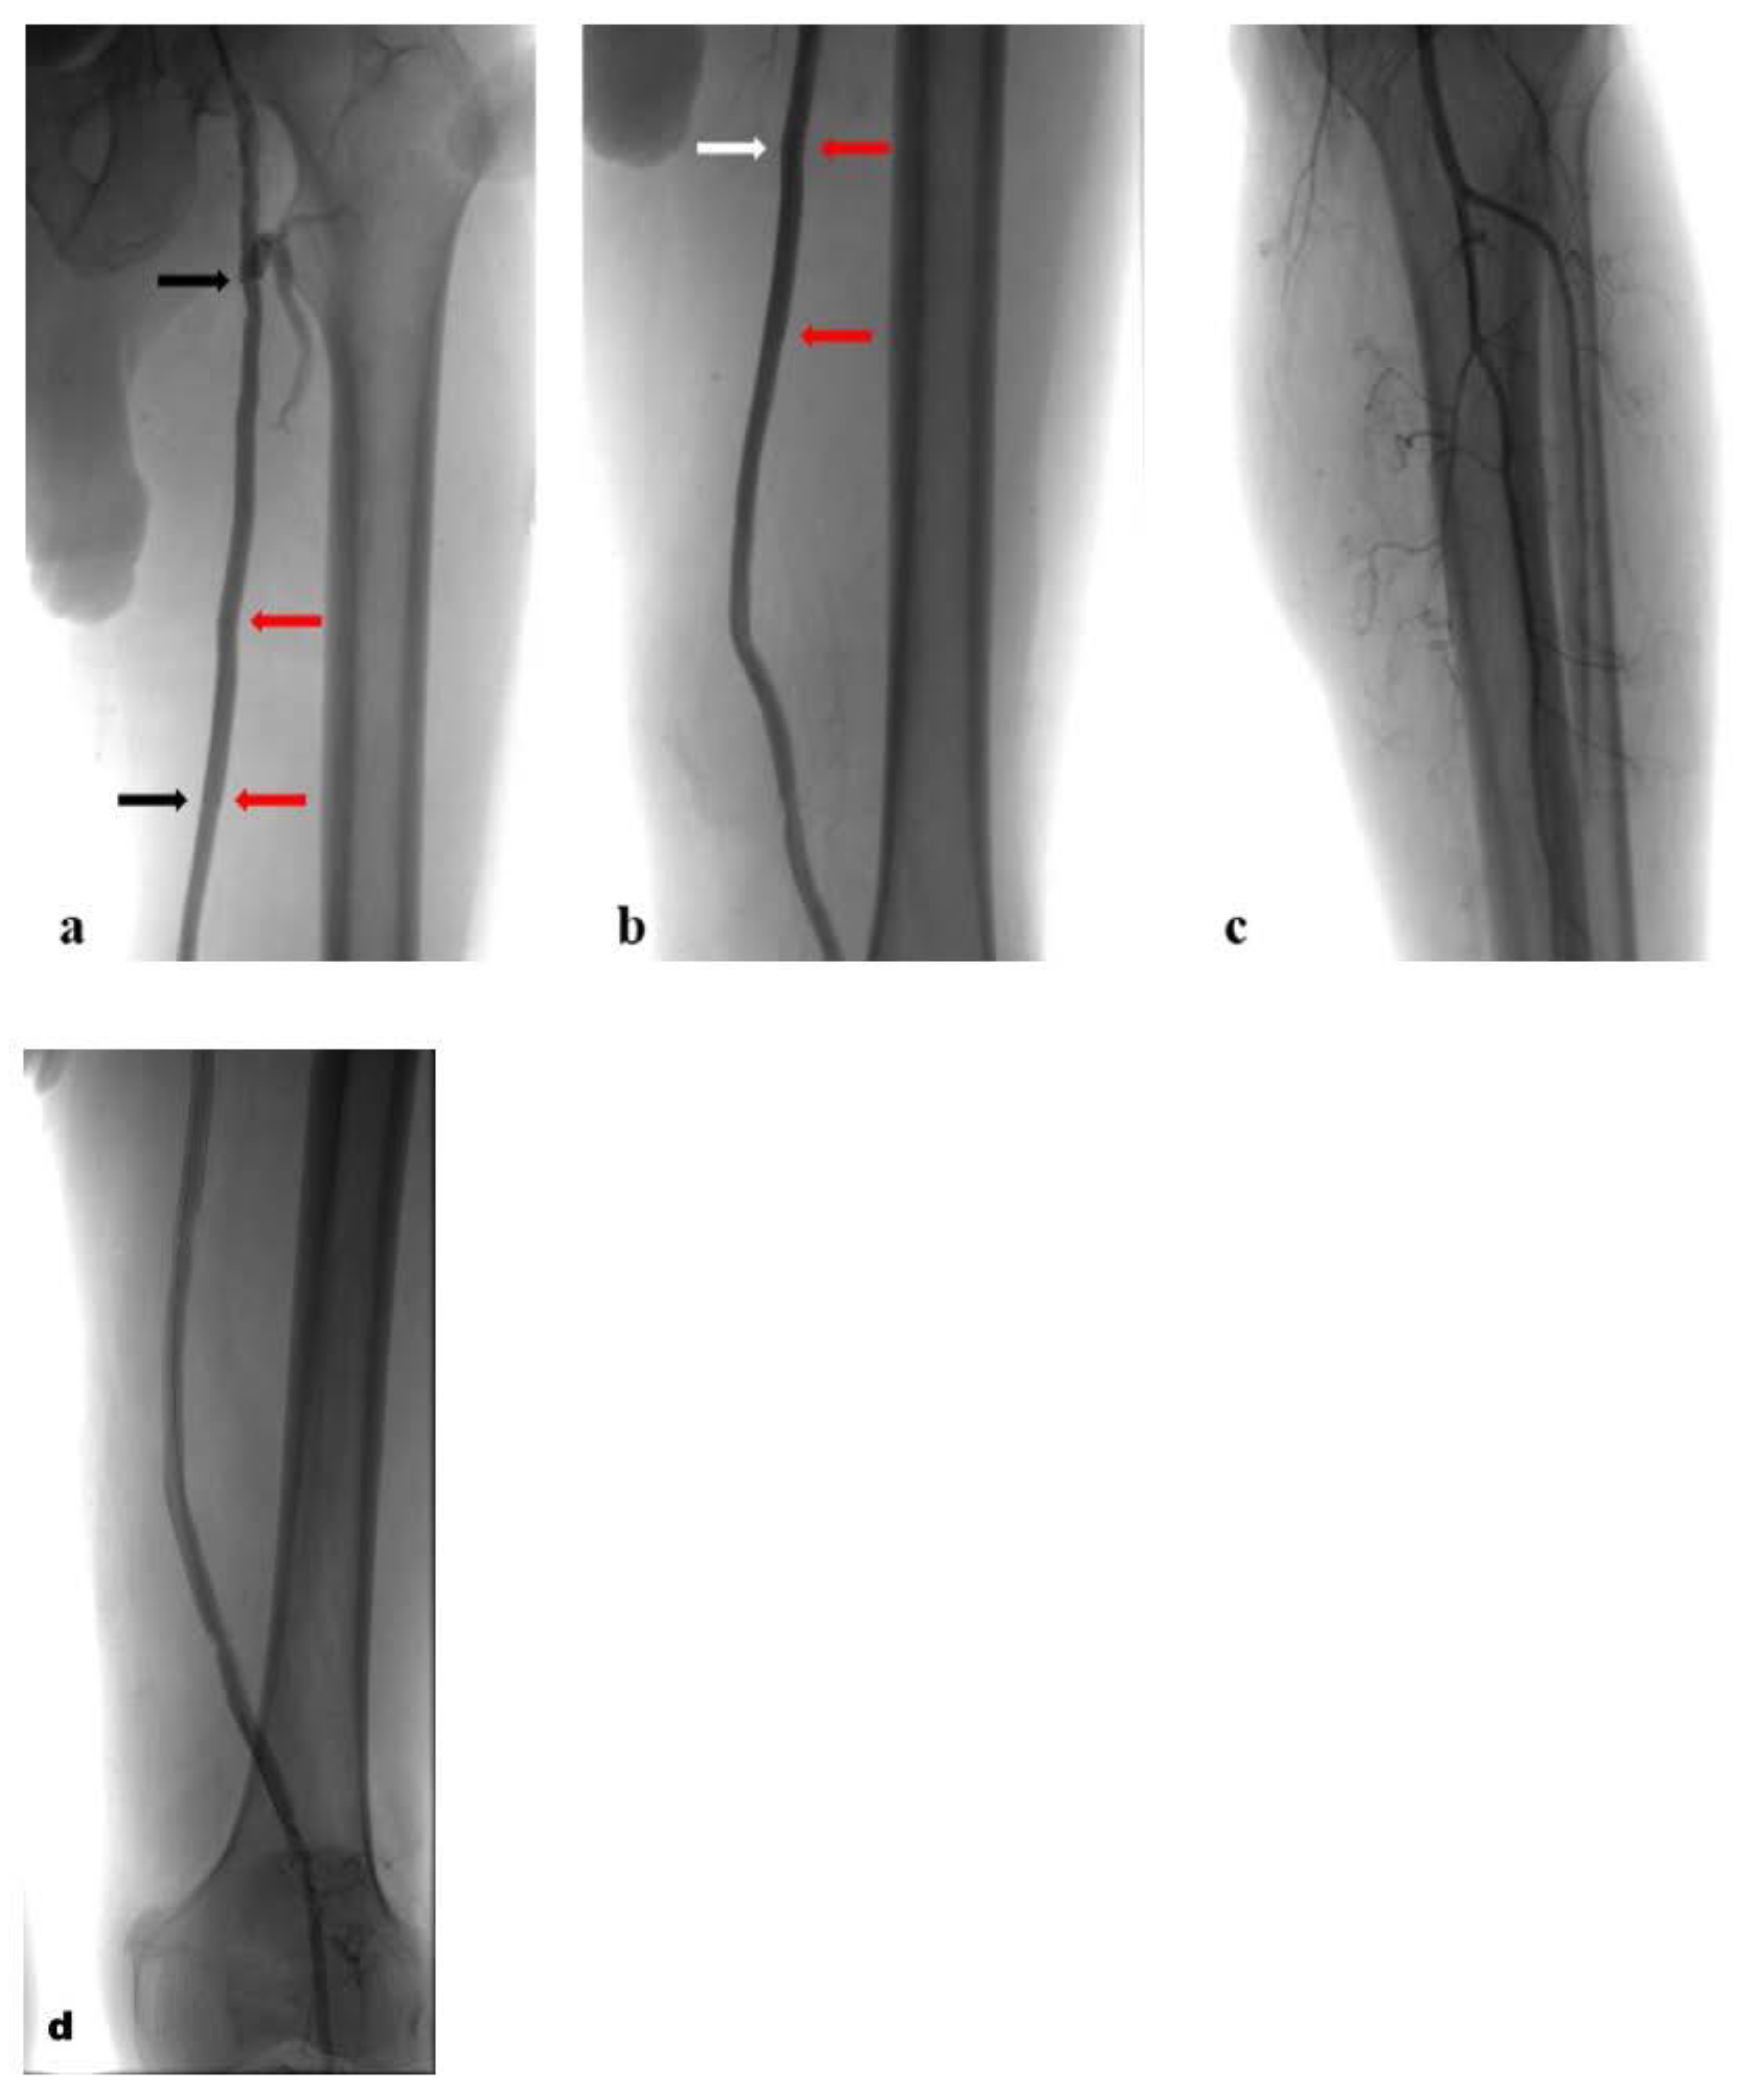

Figure 4. Postoperative angiograms with self-expanding stent grafts inside the prosthetic FB bypass: (a). proximal stent graft (black arrows) and overlap (red arrows); (b). overlap (red arrows) and distal stent graft (white arrows); (c,d). run-off.

The completion arteriogram showed the resolution of the occlusion with the direct and increased distal flow without any complications (Figure 4a–d). Successful haemostasis with FemoSeal (Terumo Europe) was obtained. The stent graft has adapted perfectly to the morphology of the lesions to be treated. The popliteal artery was reperfused to the third proximal through the collateral vessel; the vessel did not show significant atheromatous plaques. After treatment, the patient underwent therapy with clopidogrel (75 mg) + ASA (100 mg) for 2 months; next with only ASA (100 mg). Color Doppler Ultrasound after 1-3-6-9-12 months from the procedure showed patent self-expanding stent graft inside the excluded PA (Figure 5).